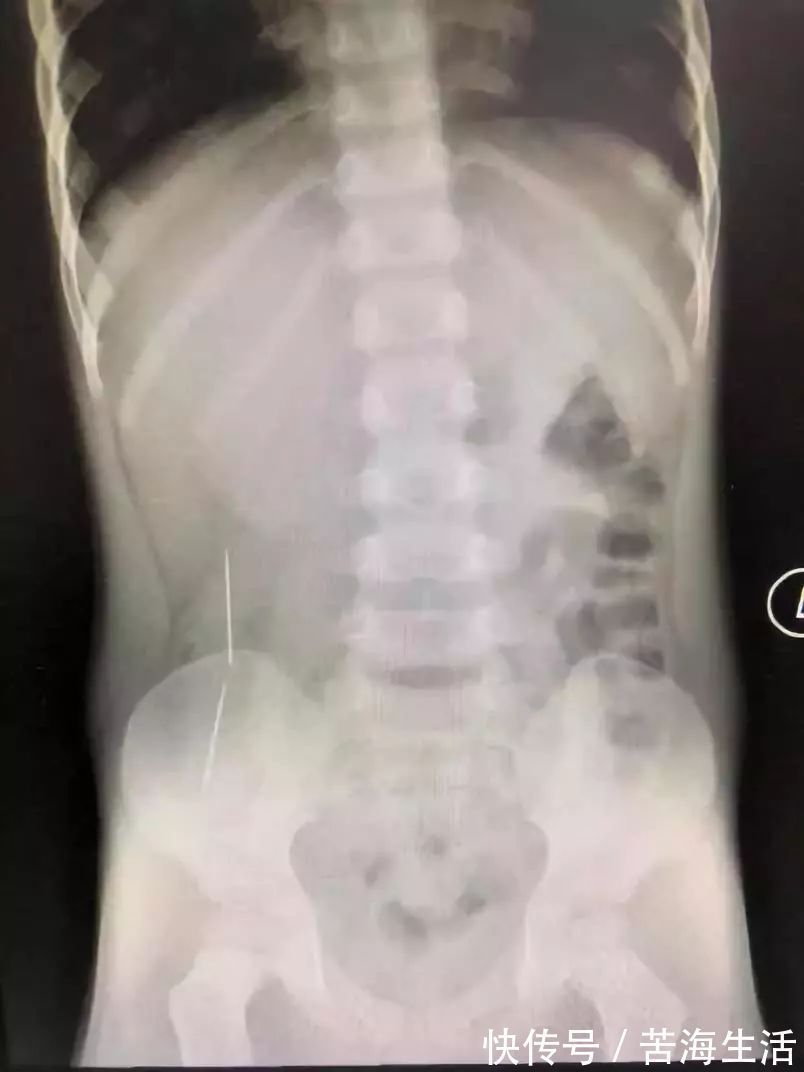

此前,深圳市儿童医院还曾接诊了一位误吞了两条绣花针的小孩彬彬。

彬彬妈妈说,他原本是吃了三根针,有一根因为呛咳当时吐了出来,剩下的两条针就全部吃了进去。 当时,看到X光片,在场所有的人都倒吸一口凉气。而且这两条已在彬彬肠胃穿游数日的绣花针,已穿透了他的肠管造成穿孔,他的腹腔内已造成了感染。情况十分不妙。

好在手术及时,没有造成大量粪便外渗,孩子转危为安。